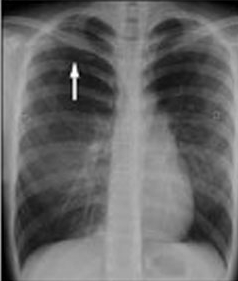

Teenaged Girl With Acute Chest Pain

A previously healthy 15-year-old girl presents with right-sided chest pain that began a few hours earlier during Spanish class.